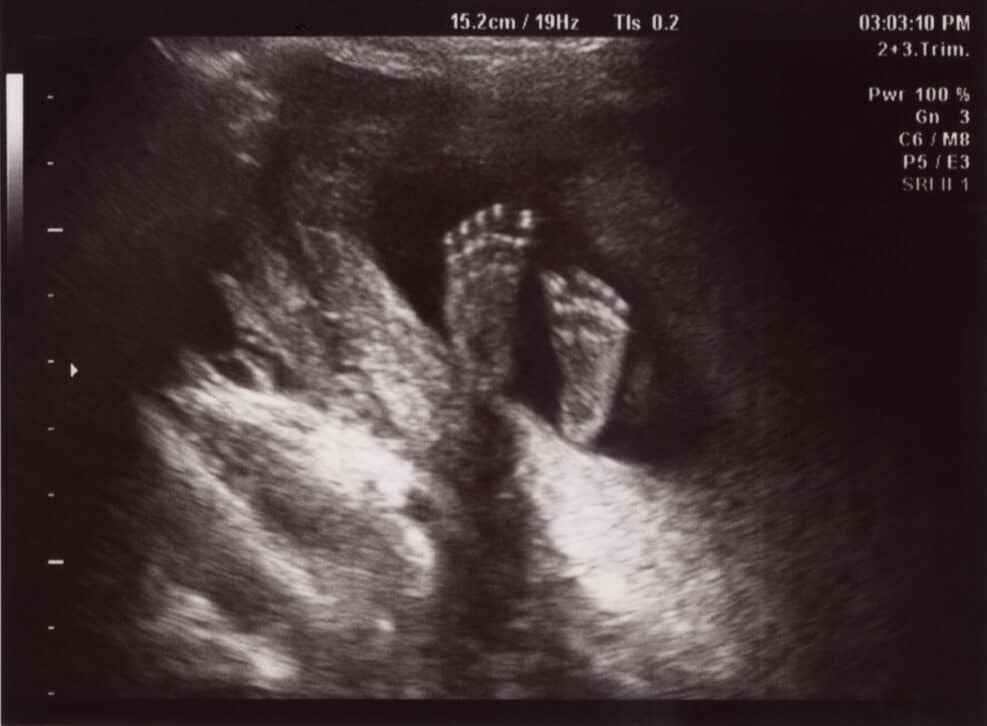

The authors imply that laws that protect unborn children are racist. But pro-lifers want more black babies born and protected from harm, not fewerEmbryology tells us that the unborn child is a human organism — distinct from but dependent upon his or her mother.